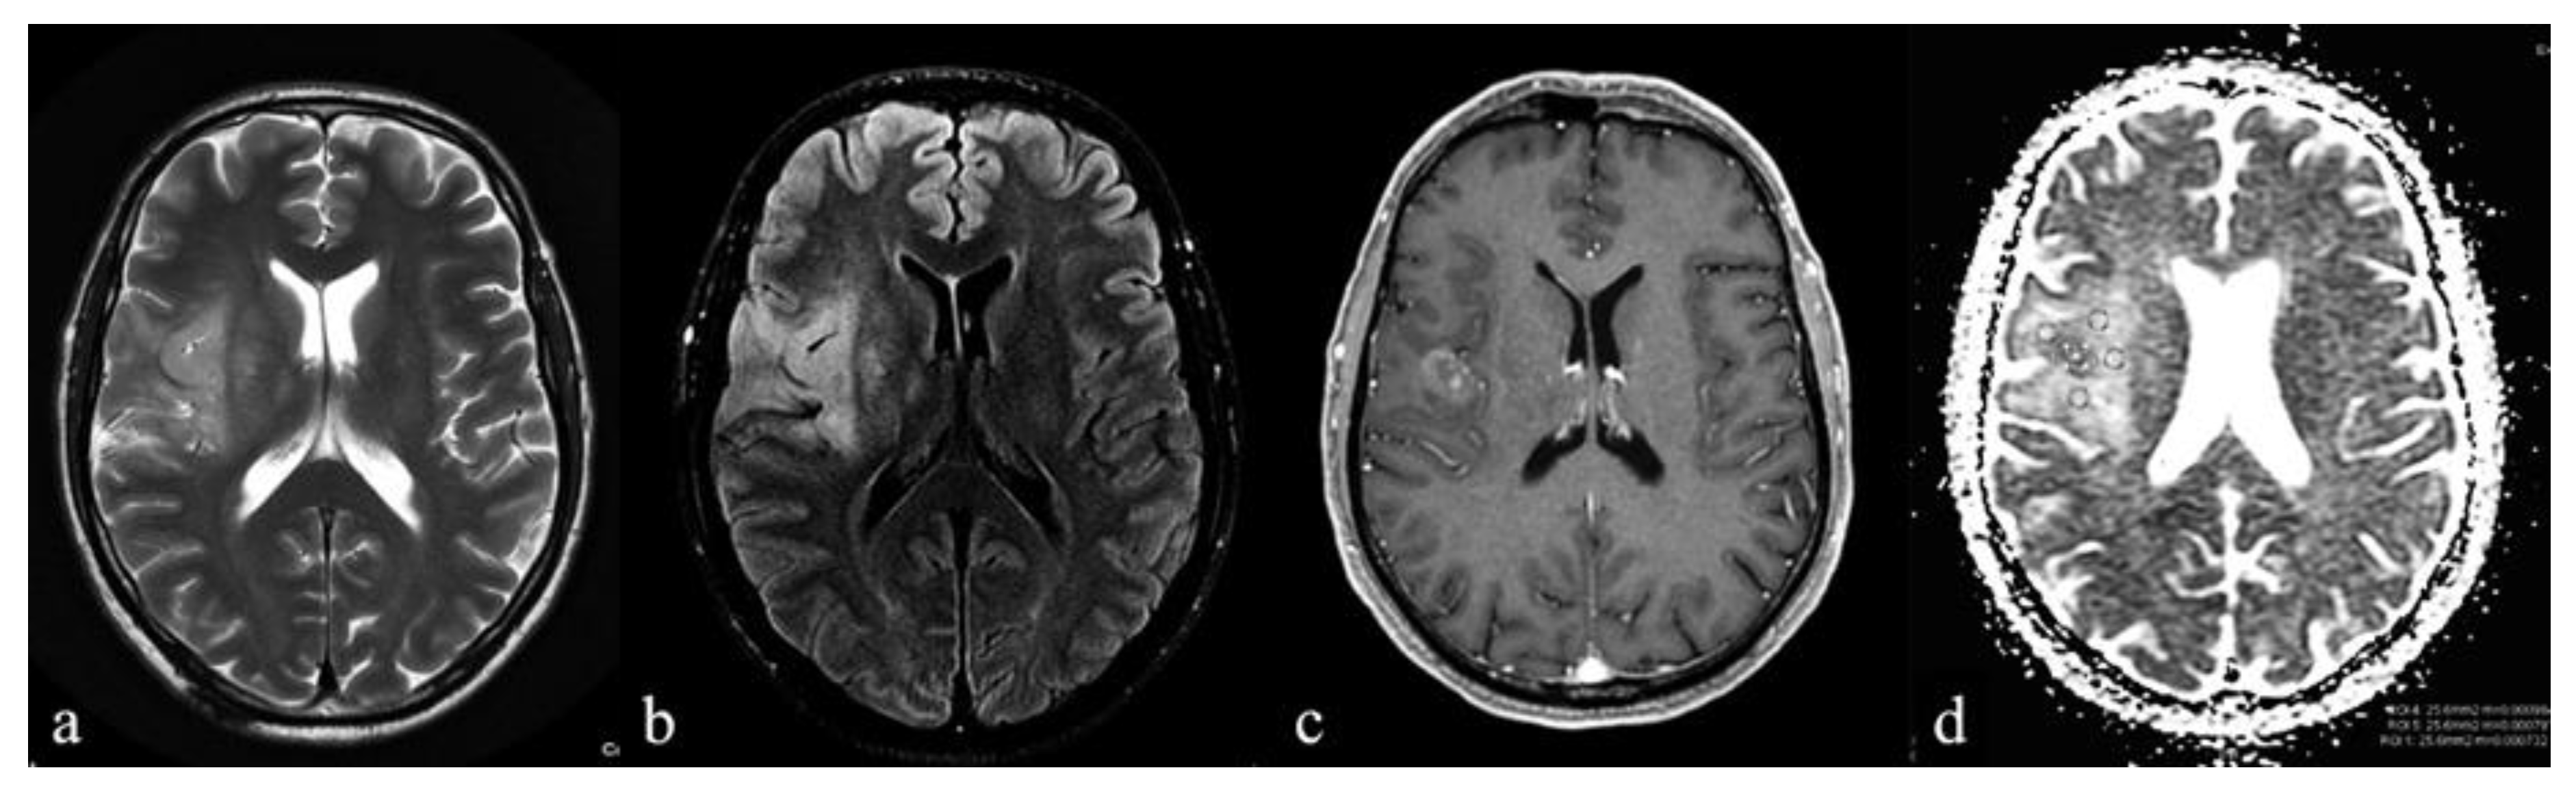

| Contrast enhancement | * 0.039 | ||

| Yes | 0 | 5 | |

| No | 10 | 7 |

| ADCm | 1.21 ± 0.19 | 0.90 ± 0.08 | 0.0004 (* 0.0012) |

| rADCm | 1.77 ± 0.33 | 1.33 ± 0.13 | 0.0021 |